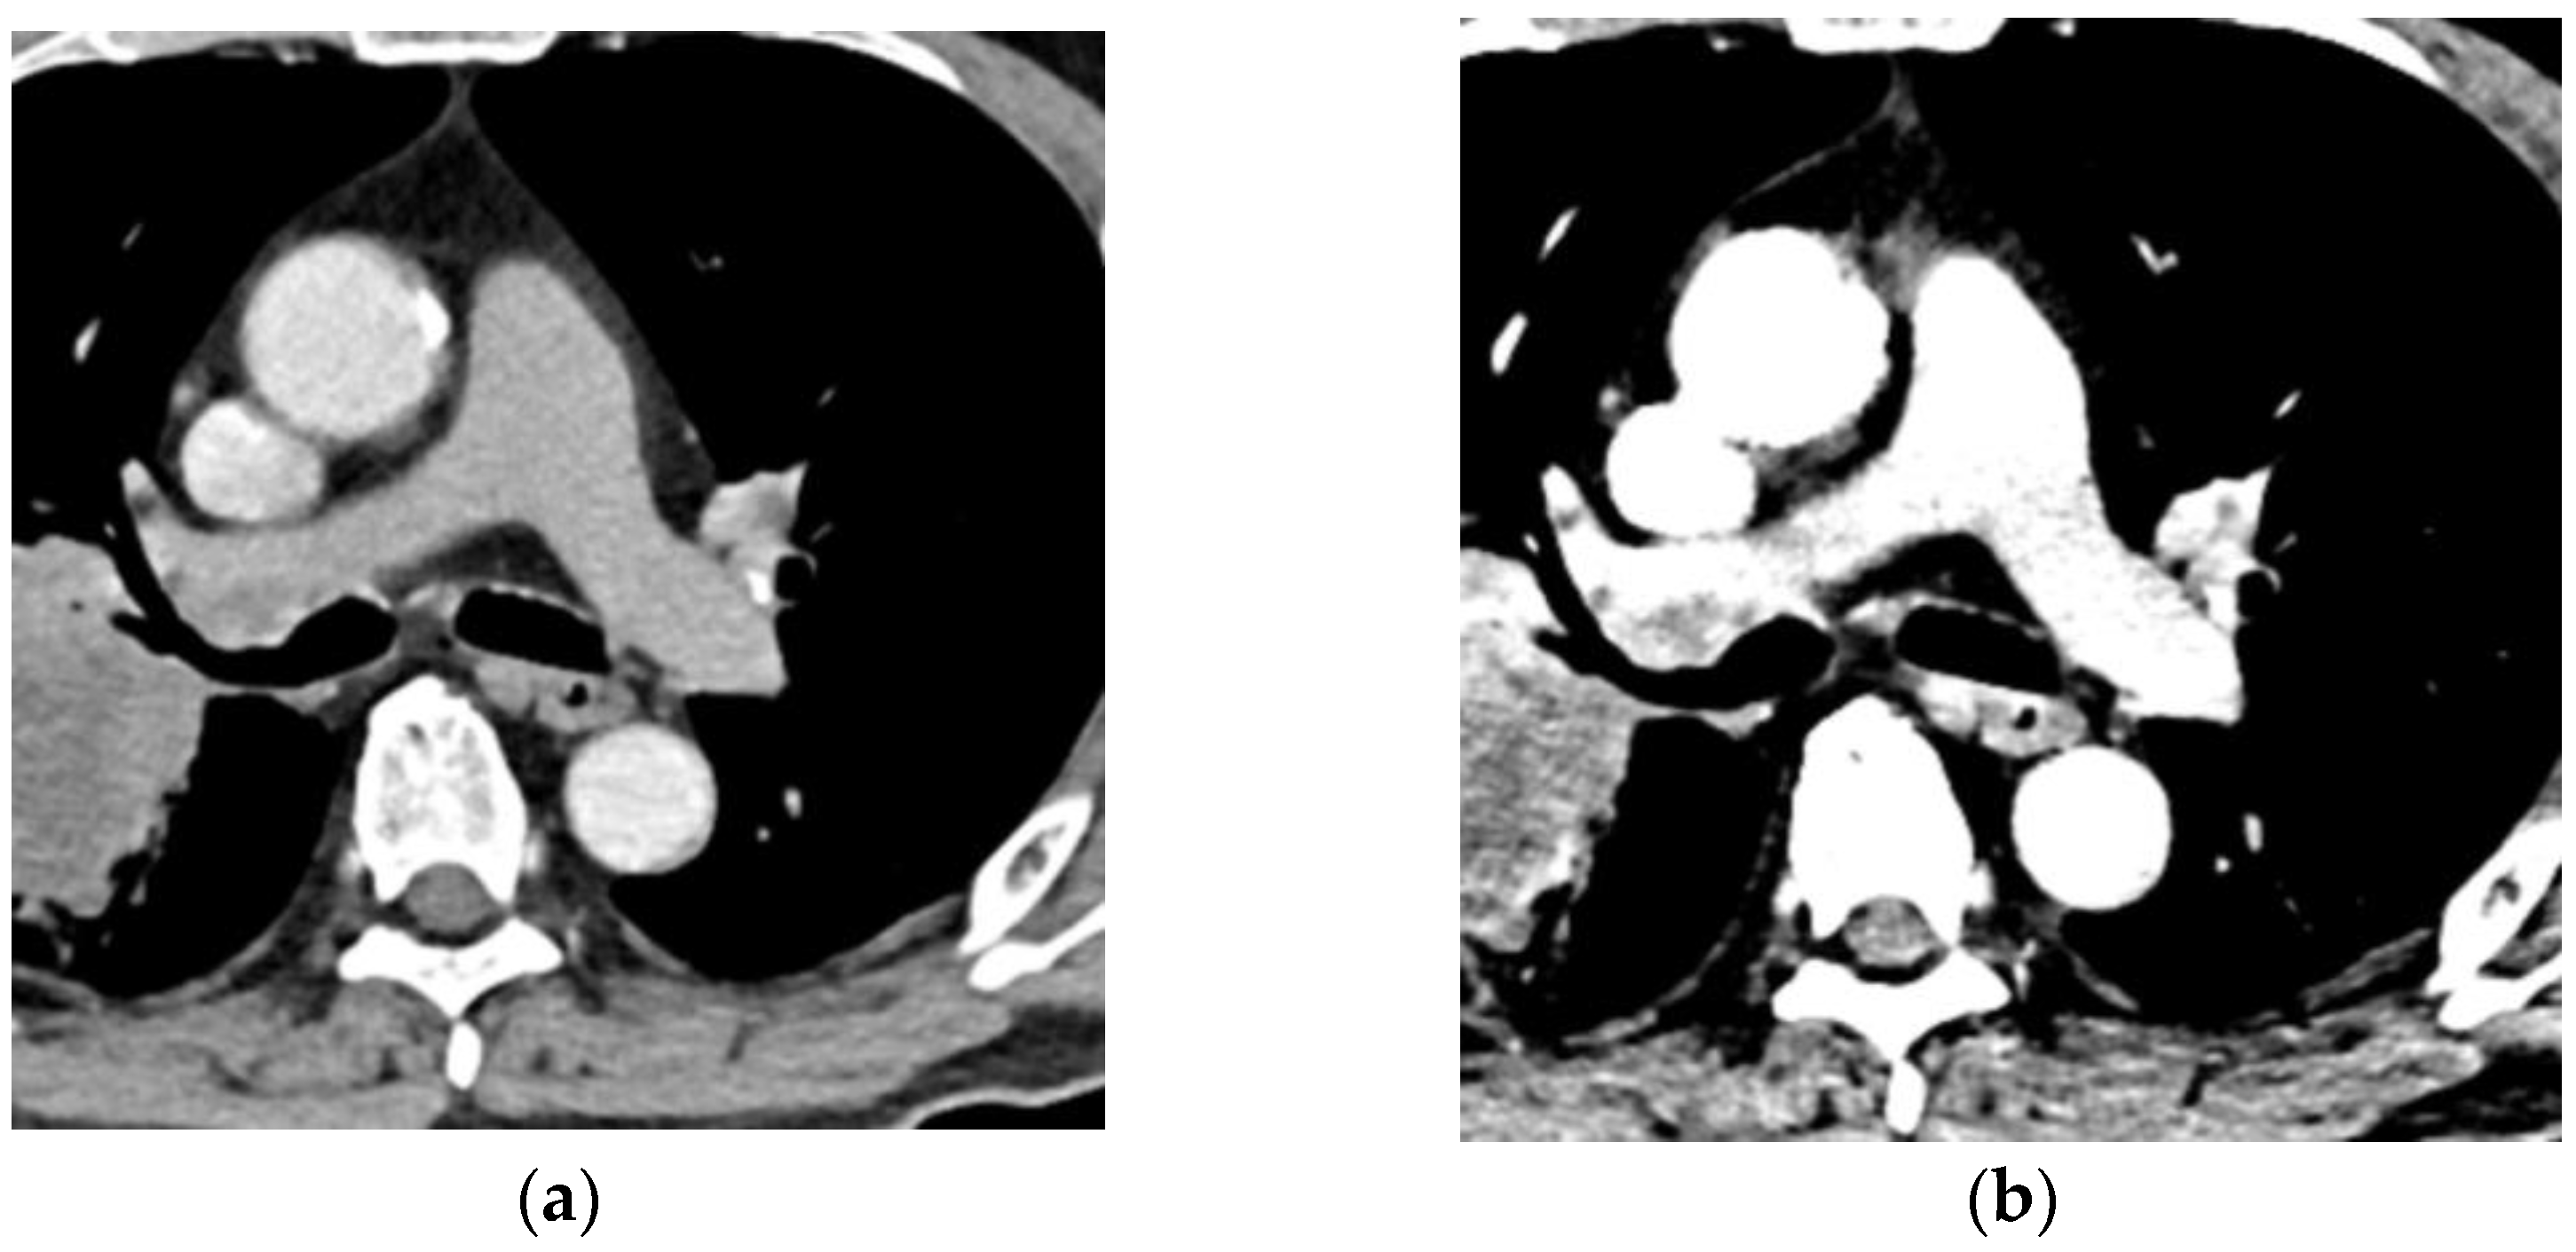

- Swift, A.J.; Dwivedi, K.; Johns, C.; Garg, P.; Chin, M.; Currie, B.J.; Rothman, A.M.; Capener, D.; Shahin, Y.; Elliot, C.A.; et al. Diagnostic accuracy of CT pulmonary angiography in suspected pulmonary hypertension. Eur. Radiol. 2020, 30, 4918–4929. [Google Scholar] [CrossRef]

- Ema, R.; Sugiura, T.; Kawata, N.; Tanabe, N.; Kasai, H.; Nishimura, R.; Jujo, T.; Shigeta, A.; Sakao, S.; Tatsumi, K. The dilatation of main pulmonary artery and right ventricle observed by enhanced chest computed tomography predict poor outcome in inoperable chronic thromboembolic pulmonary hypertension. Eur. J. Radiol. 2017, 94, 70–77. [Google Scholar] [CrossRef] [Green Version]

- Meinel, F.G.; Nance, J.W., Jr.; Schoepf, U.J.; Hoffmann, V.S.; Thierfelder, K.M.; Costello, P.; Goldhaber, S.Z.; Bamberg, F. Predictive Value of Computed Tomography in Acute Pulmonary Embolism: Systematic Review and Meta-analysis. Am. J. Med. 2015, 128, 747–759.e2. [Google Scholar] [CrossRef]

- Kang, D.K.; Thilo, C.; Schoepf, U.J.; Barraza, J.M., Jr.; Nance, J.W., Jr.; Bastarrika, G.; Abro, J.A.; Ravenel, J.G.; Costello, P.; Goldhaber, S.Z. CT signs of right ventricular dysfunction: Prognostic role in acute pulmonary embolism. JACC Cardiovasc. Imaging 2011, 4, 841–849. [Google Scholar] [CrossRef] [PubMed] [Green Version]

- Bach, A.G.; Nansalmaa, B.; Kranz, J.; Taute, B.M.; Wienke, A.; Schramm, D.; Surov, A. CT pulmonary angiography findings that predict 30-day mortality in patients with acute pulmonary embolism. Eur. J. Radiol. 2015, 84, 332–337. [Google Scholar] [CrossRef] [PubMed]